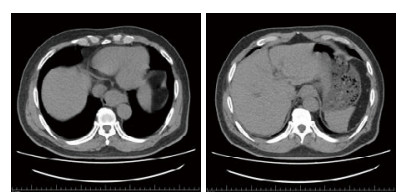

病情演变:入院后6 h患者再次出现胸骨下段、剑突下疼痛阵发加剧,伴恶心、呕吐少量暗红色血性液体,量约10 mL;胸闷较前无明显加重。复查血常规、生化、心梗三项、D二聚体。血常规:血红蛋白150 g/L。心梗三项阴性。D二聚体0.1 mg/L。诊断上消化道出血,予禁食水、抑酸、补液及对症支持治疗。请消化科会诊,综合考虑患者目前情况行急诊胃镜检查风险高,故先行腹部CT检查,见食管下段管腔狭窄,贲门胃底处可见一椭圆形略高密度影,胃内大量内容物,考虑食道裂孔疝可能(图 1)。结合目前检查,诊断:上消化道出血,急性胃潴留,食道裂孔疝?。在上述治疗基础上继续给予解痉、止痛、胃肠减压及对症支持治疗;请胸外科会诊,结合症状、体征及辅助检查,目前食道裂孔疝诊断不明确,建议观察。经过上述治疗后患者症状缓解仍不明显。后在取得患者及家属知情同意后,在严密监护下行急诊胃镜检查可见:食道大面积黏膜下出血,食管25~40 cm左侧壁可见一条状血肿改变,延至贲门口(图 2)。后收入院,给予禁食、抑酸、止血及对症支持治疗,患者胸痛、腹痛逐渐缓解。定期复查血常规,血红蛋白稳定。2016年5月23日出院随访,自觉无不适,拒绝复查胃镜。

| 食管下段管腔狭窄,贲门胃底处可见一椭圆形略高密度影,胃内大量内容物 图 1 患者腹部CT结果 |